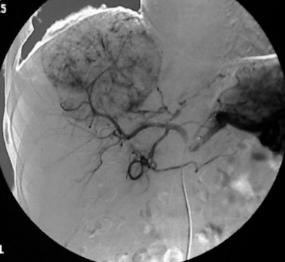

肝动脉造影显示肝内的肝癌病灶血供丰富

这是为什么呢?首先,肝癌被发现时,多数已经失去了手术切除的机会。其次,肝癌对全身化疗、放疗敏感性都不高。当然最重要的是,肝癌的介入疗效好。

肝癌的介入疗效好,与肝脏的解剖结构很有关系:肝内的血管分布与其他器官不同,它有两套血管系统,即肝动脉系统和门静脉系统。正常的肝组织主要是由门静脉供血,肝动脉供血的比例很小;而一旦发生癌变,这种供血模式就完全逆转了。肝癌组织几乎全部由肝动脉供血,门静脉不参与供血或仅有极少的供血。

因此,肝癌介入时,将混有化疗药的栓塞剂把供应癌肿的肝动脉分支完全栓塞,肝癌组织缺血缺氧,又遭受高浓度的化疗药物“浸泡”,自然就容易坏死;而正常肝组织并没有受到多少化疗药物的影响,而且由于有门静脉供血,正常肝组织也不至于缺血。因此,肝癌的“化疗栓塞”(TACE)就相当于用导弹定点打击敌人,所以才会疗效高、副作用小,自然就特别受欢迎。